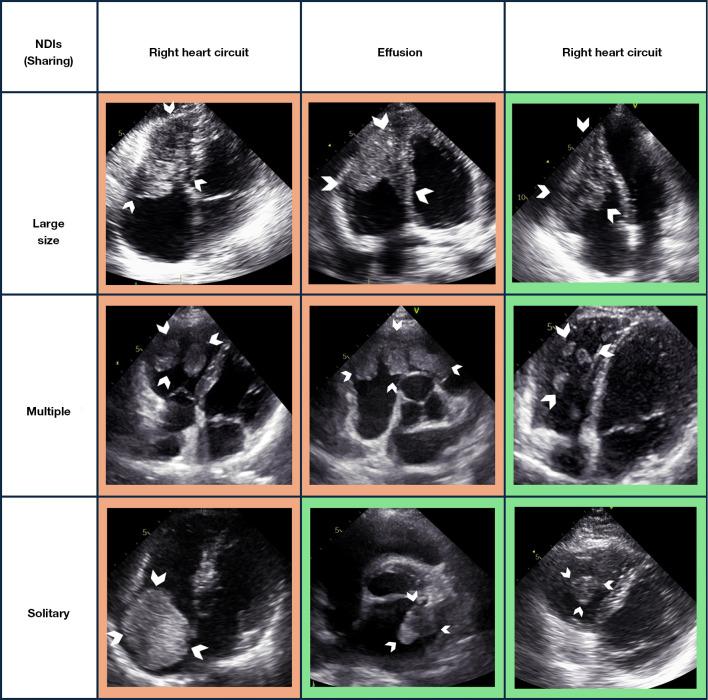

A total of 215 echocardiographic clips representing cardiac tumors from 121 patients with extracardiac malignancies were selected and divided into training and testing cohorts. The cardiac neoplasms were classified as benign or malignant based on substantial evidence. Radiomics features were extracted utilizing PyRadiomics, and a radiomics score (Rad-score) was subsequently computed through an optimized machine learning (ML) framework tailored for tumor classification. Non-experience-dependent indicators (NDIs) derived from baseline and echocardiographic assessments were ascertained and integrated with the Rad-score to construct a classification model. A composite nomogram was developed, and its predictive accuracy was benchmarked against that of junior and senior physicians using receiver operating characteristic (ROC) curves and decision curve analysis (DCA).

Significant differences in the Rad-scores and four NDIs [age, tumor location, and long and short diameters (SDs)] (all P<0.05) distinguished benign from malignant tumors. Patients with malignant cardiac tumors were more likely to be younger, for the tumor to be in the right cardiac circulatory system, be larger in size, and have a lower Rad-score. Among these indicators, the Rad-score, tumor location, and SD were shown to be independent predictors of malignancy. The integrated model demonstrated strong classification capability [area under the curve (AUC): 0.873; 95% confidence interval (CI): 0.820-0.914], which was substantiated in the test cohort (AUC: 0.861; 95% CI: 0.807-0.904). The classification performance of the generated nomogram was comparable to that of the senior doctor (AUC: 0.867 0.873, DeLong P=0.928) and surpassed that of the junior doctor (AUC: 0.867 0.669, DeLong P=0.029). DCA indicated that the nomogram was superior to the junior physician for classification tasks.

Rad-score和四个NDI(年龄、肿瘤位置以及长短径)存在显著差异(均P<0.05),可区分良性和恶性肿瘤。患有恶性心脏肿瘤的患者更可能较年轻,肿瘤位于右心循环系统,体积更大,且Rad-score更低。在这些指标中,Rad-score、肿瘤位置和短径被证明是恶性肿瘤的独立预测因素。整合模型显示出强大的分类能力[曲线下面积(AUC):0.873;95%置信区间(CI):0.820 - 0.914],在测试组中得到证实(AUC:0.861;95%CI:0.807 - 0.904)。生成的列线图的分类性能与高级医生相当(AUC:0.867对0.873,DeLong P = 0.